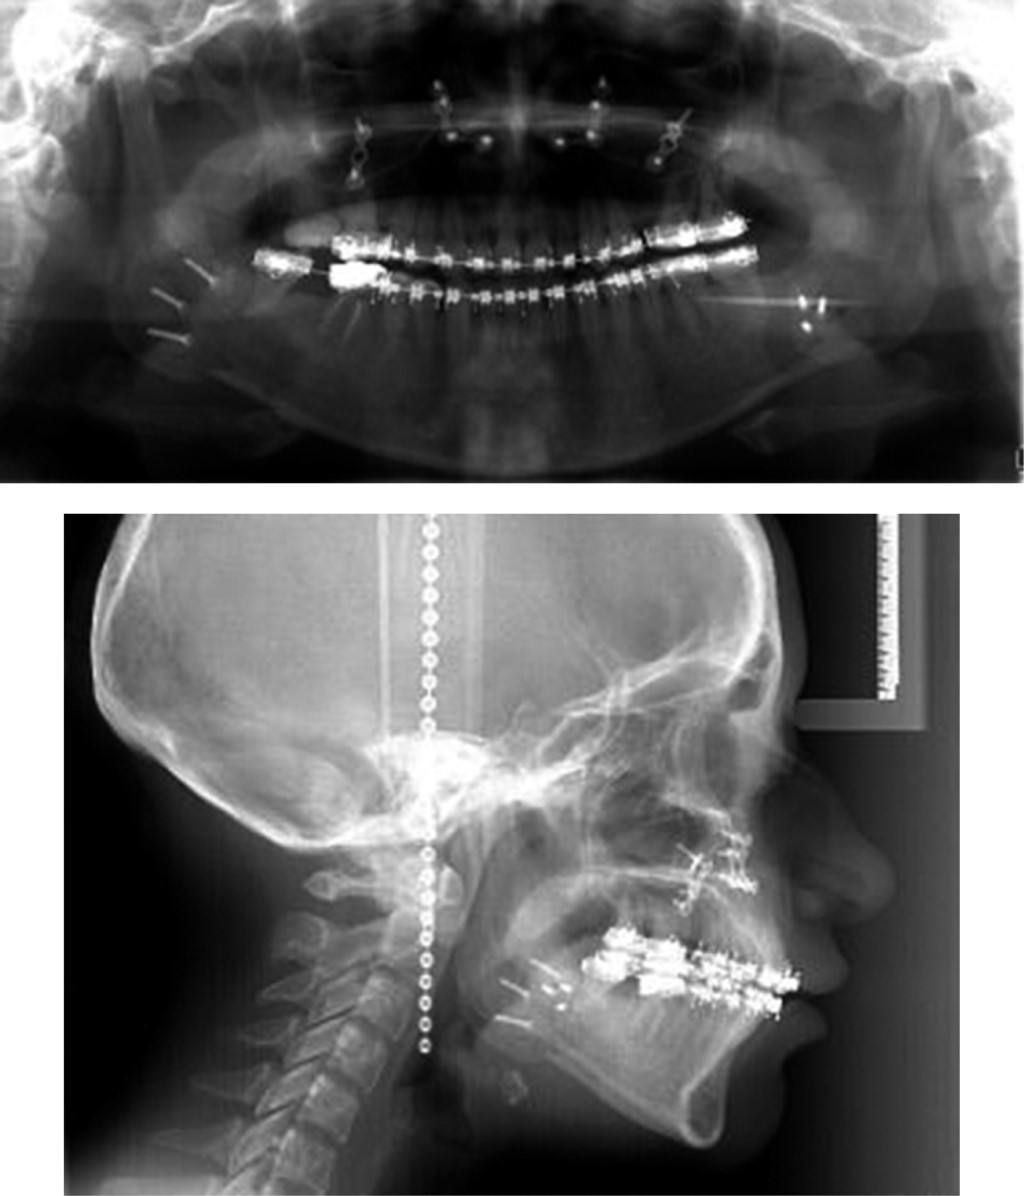

Orthopantomography: showed the presence of the 27 permanent dental organs, absent teeth 25 and 47, good crown-root relationship (1:2), an adequate level of bony ridges, asymmetrical condyles, no signs of articular disease were found (Figure 3).

Cephalometric analysis: showed class III skeletal bi-protrusive, vertical excess of the maxilla, vertical growth pattern; dolichofacial, left laterognathia, anterior crossbite, proclination of lower incisors, and retroclination of upper incisors and upper retrochelia (Figure 4).

Posteroanterior radiography: in the Ricketts posteroanterior analysis, it was found deviation of the lower dental midline, greater discrepancy on the left side and skeletal asymmetry (Figure 5).

After 12 months the case was reevaluated with the taking of study and work models, lateral and posteroanterior radiography, and orthopantomography, and together with the Surgery Department of DEPeI, UNAM, the orthognathic surgery was programmed (Figure 8).

Orthopantomography was taken to verify radicular parallelism, and control of the osteosynthesis material (Figure 10). The patient continued using elastics to correct muscular patterns of occlusal settlement. Consultation was made with the Department of Periodontics, DEPeI, UNAM, for the future placement of dental implants, where they told us to have an adequate space of 7 mm for the upper left premolar (Figure 11).

Figure 3

Figure 4

Figure 5